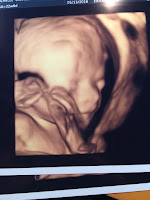

We got to take another sneak peek of Bronco today inside Mom's tummy and all looked good. He weighs around 1 lb. 5 oz. and is measuring about a week ahead of schedule. This was a big appointment in that at this same point with us Mom was hospitalized and put on bed rest. I guess the third baby is the charm because no bed rest was prescribed! Let's just hope he is this cooperative for the next 17 weeks or so and once he comes out too!